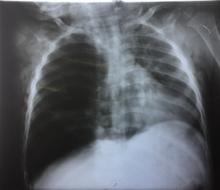

A chest x-ray (Figure 1) and computed tomography scan of the chest (Figure 2) revealed hyperinflation of the right lung, subcutaneous emphysema, and pneumomediastinum.

Rigid bronchoscopy revealed inhaled pieces of chickpeas in right main bronchus. The foreign body was extracted using forceps and suction (Figure 3). A postextraction chest x-ray showed improvement of the right lung hyperinflation (Figure 4).